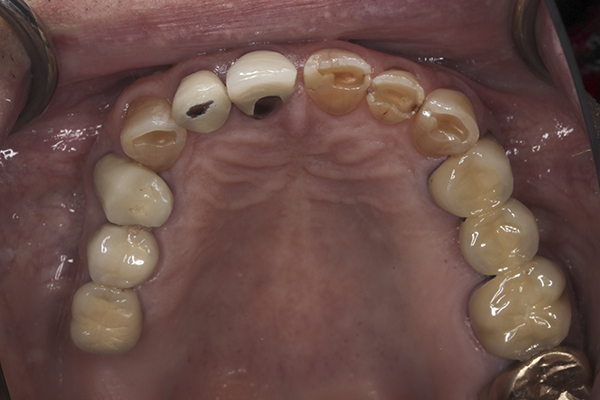

(13.) Preoperative anterior, close-up view.

Figure 13

A complete examination was performed. The patient showed no signs of joint dysfunction and there was no tenderness to palpation of any of his muscles of mastication. His mandibular range of motion was within normal limits and his function was completely comfortable. Loading of the joints in centric relation was possible with no signs of tension or tenderness. The first point of tooth contact in centric relation was noted on tooth No. 3 with a 1 mm slide forward from centric relation into maximum intercuspation. Doppler auscultation of the joints showed no signs of clicking/popping or crepitus. Examination of the teeth showed significant wear, abfractions, and erosion into the dentin of the anterior teeth. The patient also had a history of fractured porcelain on his posterior restorations and crowns coming loose. An evaluation of his occlusion revealed that the patient lacked stable centric stops on all teeth. Anterior and canine guidance was non-existent, which led to no separation of the posterior teeth during protrusive and lateral movements. His maxillary and mandibular occlusal planes were also not ideal. The patient reported no airway issues while sleeping and he had a Class 1 Mallampati score. The patient was advised to consult with his physician to evaluate for an acid reflux issue.

A complete set of records was taken, including diagnostic photographs (Figure 3 through Figure 16), diagnostic impressions, a centric relation bite record, and a facebow transfer. The models were mounted onto an articulator and, along with the photographs, a preliminary workup of the case was completed. An ideal treatment plan consisting of a fullmouth rehabilitation with full-coverage restorations to idealize the planes of occlusion and to properly restore the anterior teeth was presented to the patient. The patient was not interested in extensive work on his posterior teeth because of his age and the fact that he was only interested in “something that will last another 10 years because that’s about how long I’ll be around.” He was only concerned with addressing the anterior teeth and would not accept a treatment plan replacing the restorations on his posterior teeth. Because the author wanted to help the patient with his esthetic concern while still addressing the functional issues, an alternative compromise treatment plan was agreed upon, which involved definitive full coverage restorations in the anterior and composite bonding in the posterior. The patient was fully aware that this treatment plan was a compromise and that the posterior composites will most likely require repair over time. By stabilizing the anterior contacts, anterior guidance, and canine guidance, the author felt comfortable placing bonded composite restorations on the posterior teeth to improve the plane of occlusion. The author also suggested the use of a nighttime occlusal appliance, but the patient refused this option. A guard worn at night would have increased the longevity of the posterior composites, as well as further protected the anterior restorations.